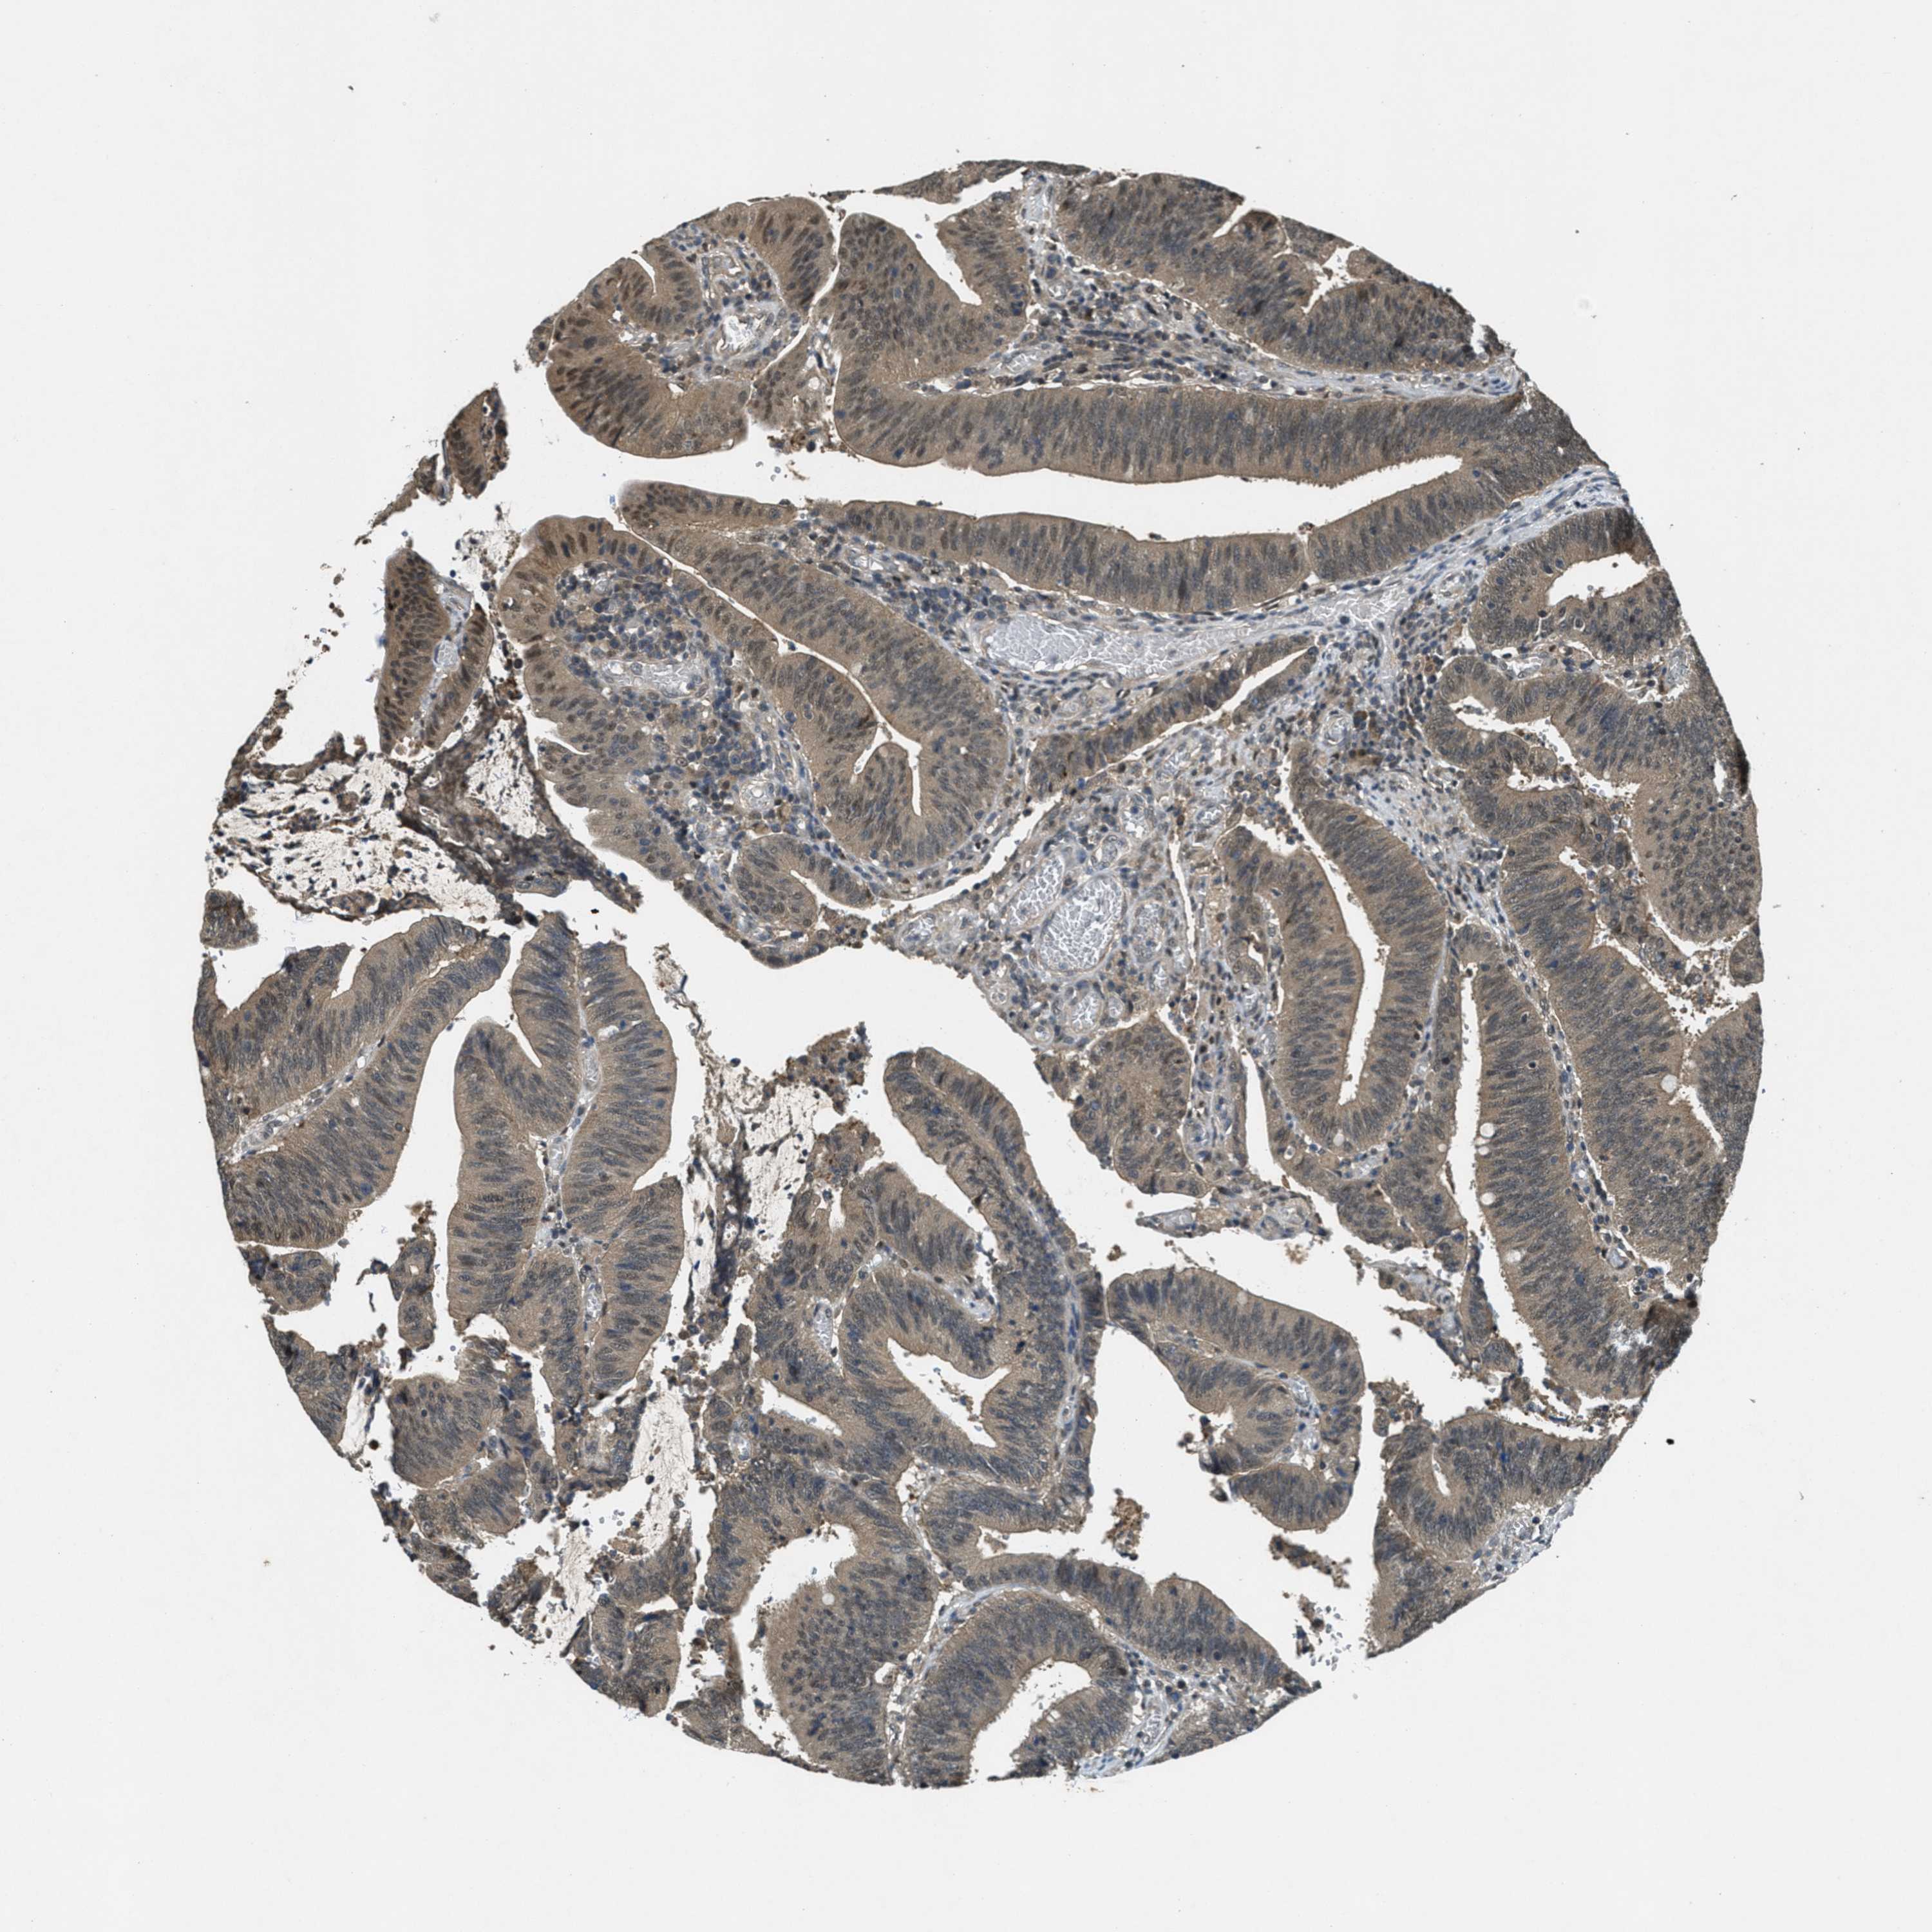

CANCER COLORECTAL CANCER Show tissue menu

Colorectal cancer

Human cancer

Colon adenocarcinoma